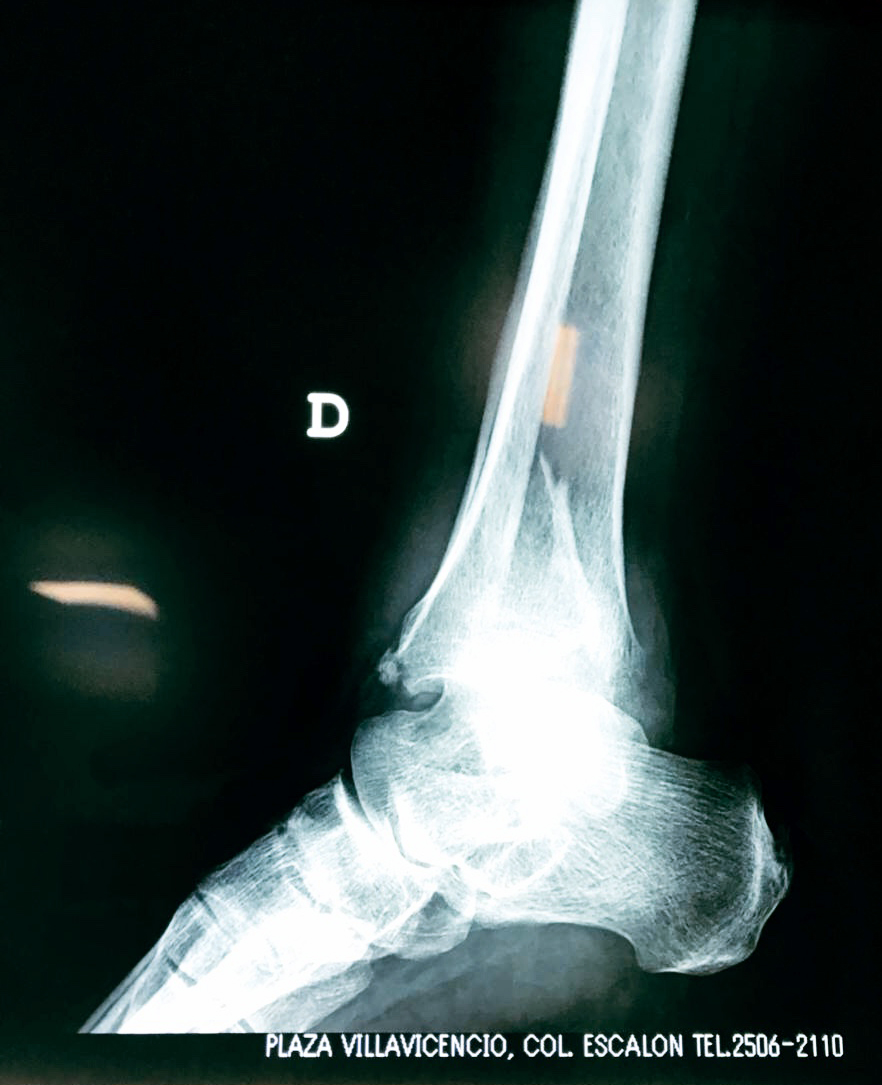

Una fractura de tobillo es la rotura de uno o más de los huesos del tobillo. Estas fracturas pueden ser:

Algunas fracturas de tobillo pueden requerir cirugía si:

- Los extremos de los huesos están desalineados entre sí (desplazados).

- La fractura se extiende hasta la articulación del tobillo (fractura intra-articular).

- Los tendones o ligamentos (tejidos que sujetan los músculos y los huesos entre sí) están rotos.

- El médico cree que sus huesos probablemente no sanen apropiadamente sin cirugía.

- El médico considera que la cirugía puede permitirle una recuperación más rápida y confiable.

Cuando se necesita cirugía, es probable que esta implique el uso de clavijas de metal, tornillos o placas para sostener los huesos en su lugar mientras la fractura se consolida. Los elementos de soporte pueden ser temporales o permanentes.